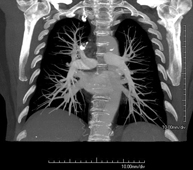

- Angio-TC Arterias pulmonares (Estudio TEP, Tromboembolismo Pulmonar) Prueba diagnóstica que consiste en el estudio de las arterias pulmonares mediante el empleo de un equipo de TC (Tomografía Computarizada) obteniendo imágenes bi y tridimensionales. En este estudio es imprescindible el uso de contraste yodado, el cual permitirá una mejor definición anatómica. Esta prueba está principalmente indicada en los casos de sospecha de tromboembolismo pulmonar (TEP) para descartar o confirmar la presencia de coágulos sanguíneos en el interior de las arterias. Prueba diagnóstica que consiste en el estudio de las arterias pulmonares mediante el empleo de un equipo de TC (Tomografía Computarizada) obteniendo imágenes bi y tridimensionales. En este estudio es imprescindible el uso de contraste yodado, el cual permitirá una mejor definición anatómica. Esta prueba está principalmente indicada en los casos de sospecha de tromboembolismo pulmonar (TEP) para descartar o confirmar la presencia de coágulos sanguíneos en el interior de las arterias.

- Angio TC d'artèries pulmonars (estudi Tep, tromboembolisme) Prova diagnòstica que consisteix en l'estudi de les artèries pulmonars mitjançant l'ús d'un equip de TC (Tomografia Computaritzada) i amb l'obtenció d'imatges bi i tridimensionals. En aquest estudis és imprescindible l'ús de contrast iodat, que permet una millor definició anatòmica. Aquesta prova està principalment indicada en els casos en els quals hi hagi sospita de tromboembolisme pulmonar (TEP) per descartar o confirmar la presència de coàguls sanguinis a l'interior de les artèries. Prova diagnòstica que consisteix en l'estudi de les artèries pulmonars mitjançant l'ús d'un equip de TC (Tomografia Computaritzada) i amb l'obtenció d'imatges bi i tridimensionals. En aquest estudis és imprescindible l'ús de contrast iodat, que permet una millor definició anatòmica. Aquesta prova està principalment indicada en els casos en els quals hi hagi sospita de tromboembolisme pulmonar (TEP) per descartar o confirmar la presència de coàguls sanguinis a l'interior de les artèries.